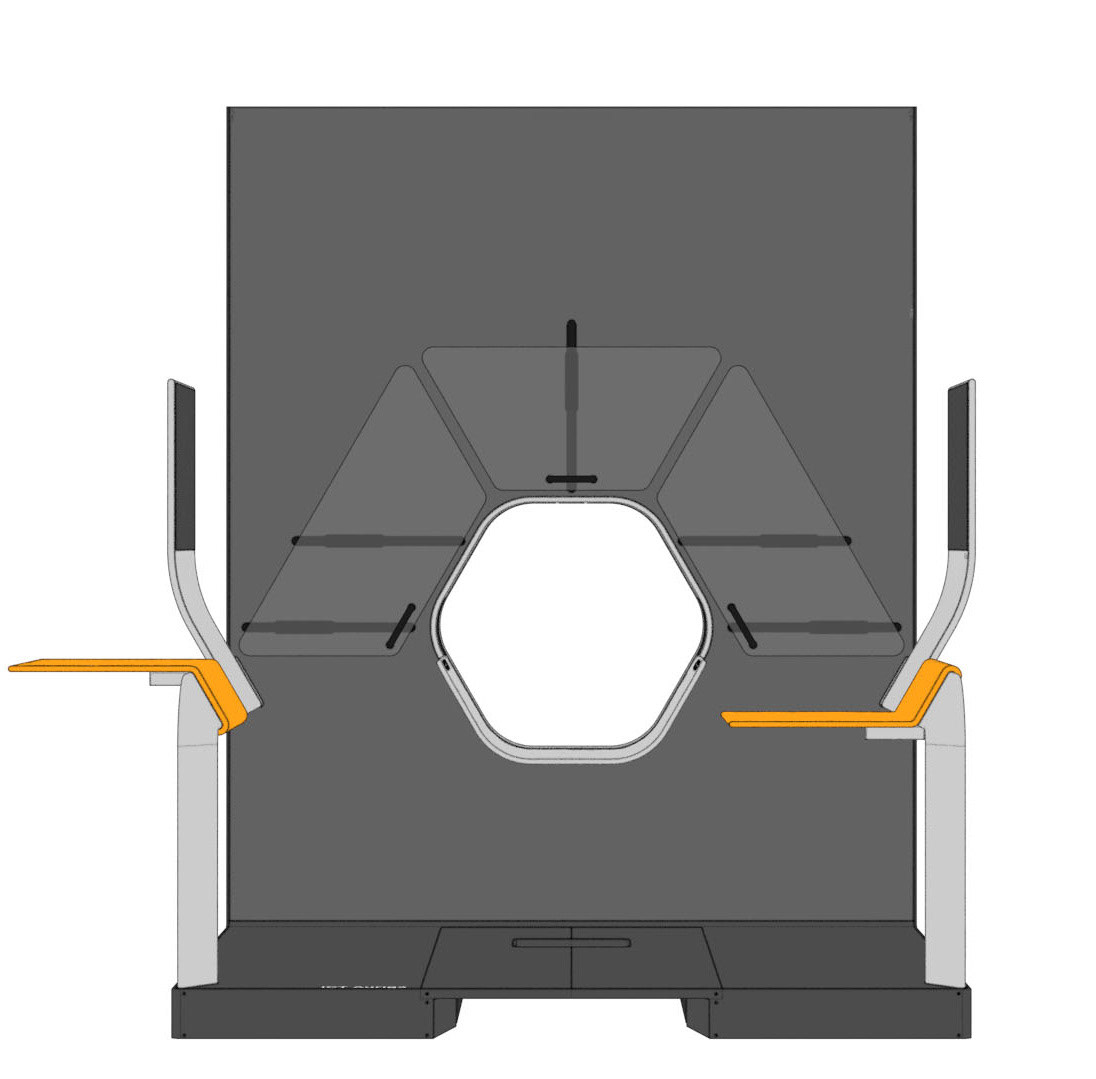

Various tables can be suspended on the railing. This enables the individual positioning of surgical instruments and devices. To relieve the interventionists, it is also possible to lean against the railing, similar to a standing seat in a gondola or tram. In addition, the railing offers protection against a potential fall from the platform.

The central design feature is the hexagonal gantry opening. It provides space for the lamps and displays. The large fronts of the gantry offer space for a display of different coloured patterns and animations, which visualize the radiation. These can be individually selected and adapted together with the overall height of the gantry. The patterns pick up on the hexagonal shape of the gantry opening and set it off. To protect the interventionists from radiation, lead glass panels and a radiation protection tray are installed. The sliding lead glass panels allow individual adaptation to the patient and the interventionists working space. The tray serves to protect the abdomen and offers a lot of foot space as well as a front leaning aid for a safe stand.

For direct inspection of the CT scans, there is one large overview screen per side and a small detail screen inside the gantry. The control interface of the gantry is located inside the lower trough, which protects the abdomen of the interventionists from radiation. In addition, there is a foot pedal on the floor that allows hands-free activation of the CT imaging.